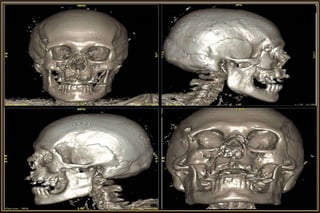

CT ideal for Bony & Traumatic Manifestations

• Bony detail or calcification

Computed Tomography

Major Considerations

• Slice thickness

• Imaging plane – Axial / Coronal / Sagittal

• Tissue window – Soft or Brain / Bone

• Contrast enhancement – Iohexol (46% Iodine)

• Modification of CT procedure